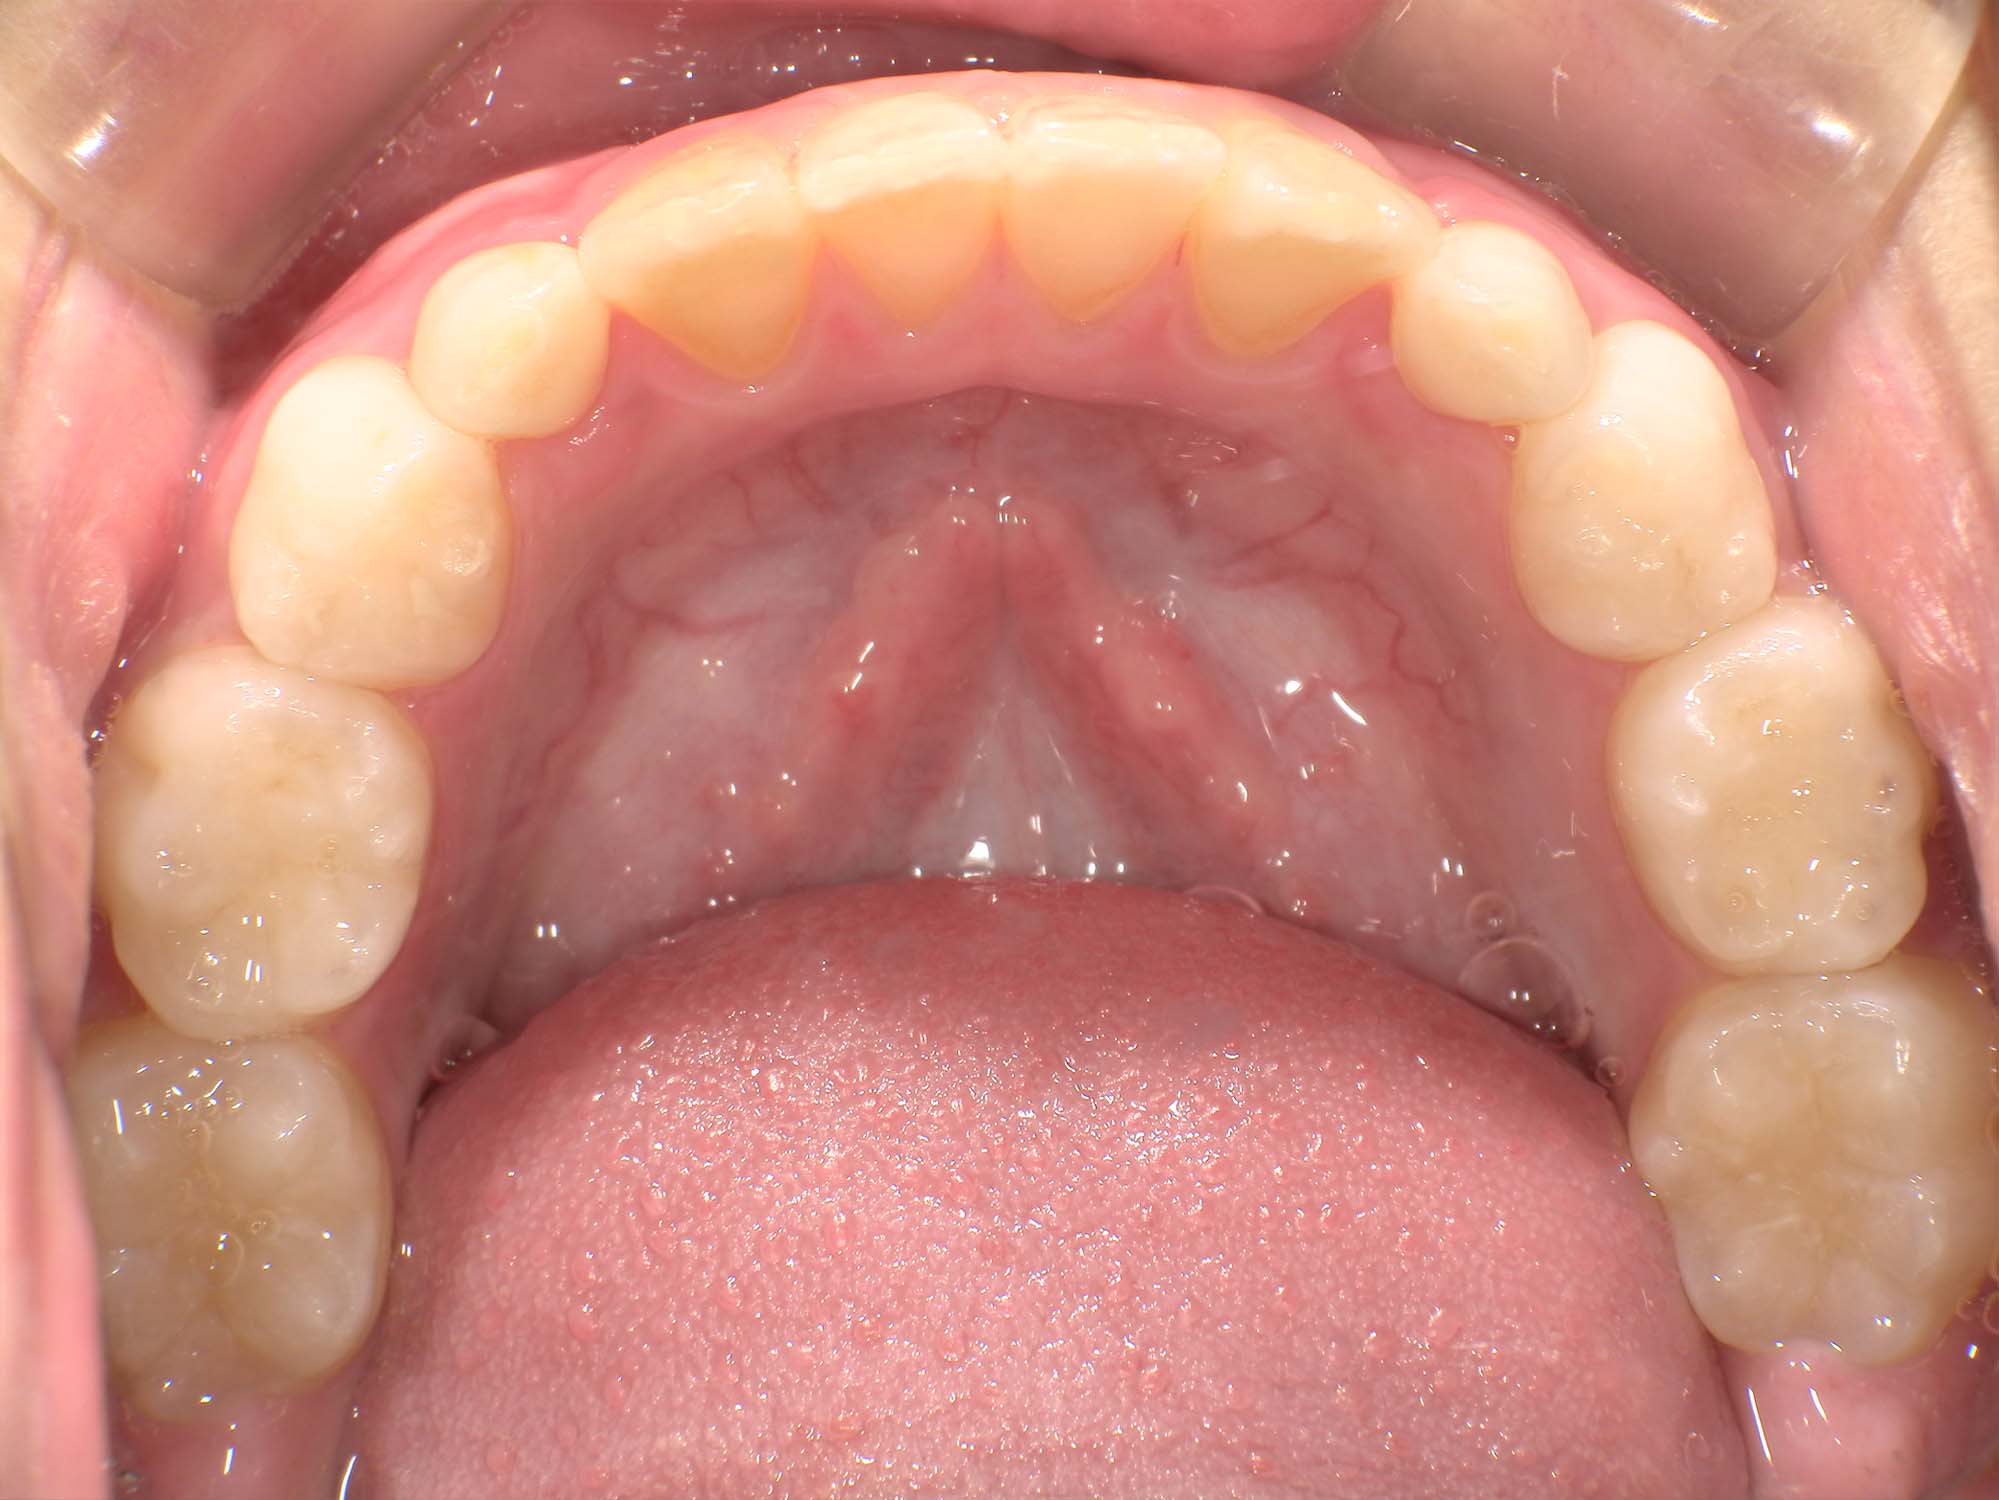

| 年齢・性別 | 8歳11ヶ月の男児 |

|---|---|

| 主訴 | 上顎の永久歯の位置がおかしいとのことで来院。萌出していない右上の前歯の状態に不安を抱えられていました。 |

| 治療期間・回数 | 約3年2ヶ月 |

| 費用 | 440,000円(税別) |